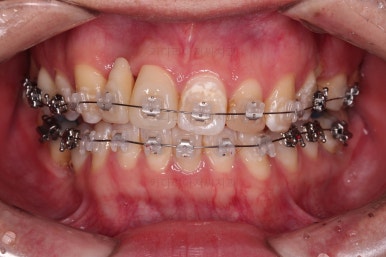

장치를 부착한 모습입니다.

이번 환자분은 자가결찰 세라믹(엠파워 클리어) 장치를 선택하셨고요.

잔존유치는 발치했고, 앞니 가짜치아는 벗겨내고 새로운 가짜치아를 와이어에 묶어주었습니다.

다행히 매복되었던 영구치는 잘 이동하였고요.

임플란트 자리도 적당한 크기로 점점 넓혀갑니다.